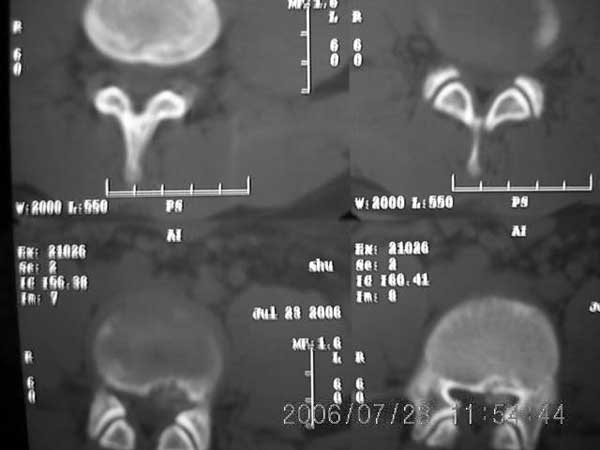

以下是引用xiaoniu在2006-7-23 12:47:00的发言:[br]椎体后缘软骨结节[br]【发病机制】尚未完全清楚,存在多种学说。一般认为青少年时期,脊柱负重压力及髓核膨胀性压力下,椎间盘组织通过椎体薄弱区疝入椎体内,局部骨小梁吸收被椎间盘组织代替形成软骨结节,周围骨小梁出现反应性硬化,逐渐形成骨壳包绕软骨结节。 椎体后缘软骨结节是椎间盘组织向后疝入椎体后缘的结果,为边缘性软骨结节的一种特殊类型。[br]【ct表现】椎体后缘类圆形、多囊状或不规则形的骨质缺损区,大小不一,位于椎体后缘正中或偏侧,其ct值等同于同层面的椎间盘,70~90hu,边界清楚,常有薄厚不一的硬化带。缺损区后方骨块突入椎管内,椎管狭窄,硬膜囊受压。[br]【鉴别诊断】本病诊断不难,需与以下疾病鉴别[br] 1 椎间盘突出钙化。2 后纵韧带骨化。3退变形成的骨赘。4锥体后缘撕裂性骨折。[br]上述疾病骨块影的形态及位置均各具特征,且椎体后缘均无低密度的骨结软节,鉴别不难。[br][br][本贴已被 xiaoniu 于 2006-7-23 12:52:32 修改过]